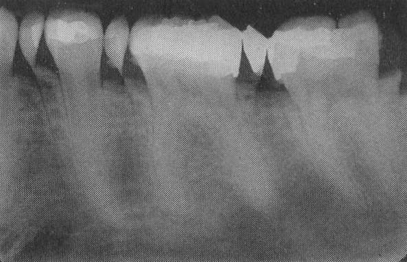

Double exposure